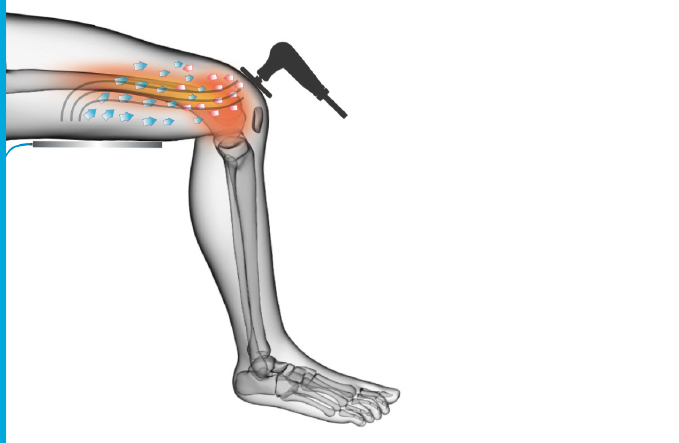

רדיו-פרקונסיה (Tecar)

עובד על עומק הרקמות, משחרר נוקשות ומסייע בשיקום מהיר יותר